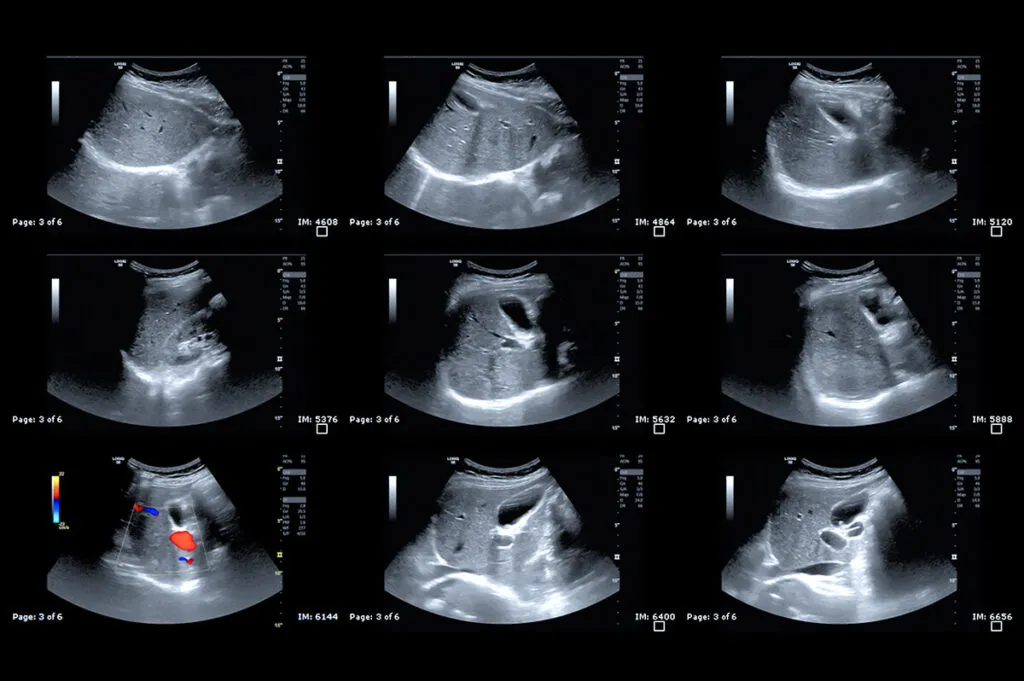

USG jamy brzusznej: dlaczego jest to badanie pierwszego wyboru i co może wykryć?

Ultrasonografia (USG) jamy brzusznej jest badaniem pierwszego wyboru z kilku kluczowych powodów: jest nieinwazyjna, bezbolesna, bezpieczna (nie wykorzystuje promieniowania jonizującego), szeroko dostępna i stosunkowo tania. Pozwala na dynamiczną ocenę wielu narządów w czasie rzeczywistym. Podczas USG lekarz może ocenić:

- Wątrobę: Jej wielkość, strukturę, obecność zmian ogniskowych (torbiele, guzy), stłuszczenie.

- Pęcherzyk żółciowy i drogi żółciowe: Obecność kamicy żółciowej, cechy zapalenia pęcherzyka, poszerzenie dróg żółciowych.

- Trzustkę: Jej wielkość, strukturę, obecność zmian zapalnych (np. w ostrym zapaleniu trzustki), torbieli czy guzów.

- Śledzionę: Jej wielkość i strukturę.

- Nerki i pęcherz moczowy: Wielkość, kształt, obecność kamieni nerkowych, torbieli, guzów, zaleganie moczu w pęcherzu.

- Duże naczynia krwionośne: Takie jak aorta brzuszna (może wykryć tętniak aorty).

- Wyrostek robaczkowy: W przypadku podejrzenia zapalenia wyrostka robaczkowego, USG może uwidocznić jego powiększenie i cechy zapalenia.

- Narządy rodne u kobiet: Może wykryć torbiele jajników, mięśniaki macicy czy inne patologie.

USG jest więc niezwykle wszechstronnym narzędziem, które często pozwala na szybkie postawienie diagnozy lub ukierunkowanie dalszej diagnostyki.